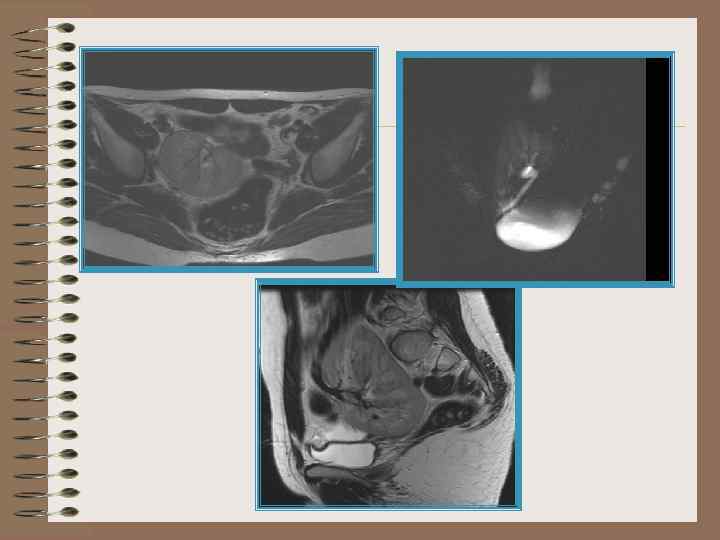

Тазовая дистопия

Тазовая дистопия. Беременность лоханка